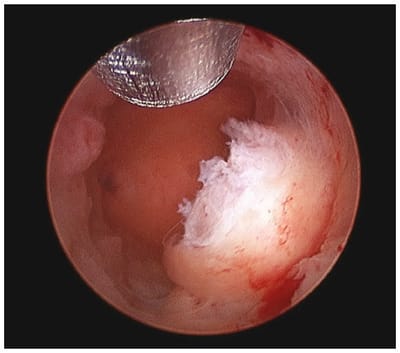

Histeroscopia Operativa

La histeroscopia operatoria es la esencia de la cirugía mínimamente invasiva. Utiliza una cámara operatoria insertada en la cavidad uterina para solucionar problemas localizados allí sin tener que recurrir a una histerectomía. Además de los cólicos menstruales, es una recuperación rápida sin incisiones.

Polypectomy

Los pólipos son una causa común de sangrado menstrual abundante, sangrado a mitad del ciclo o sangrado poco después del coito. La extirpación de estos pólipos con un histeroscopio puede reducir estos problemas de sangrado sin comprometer su útero o fertilidad.